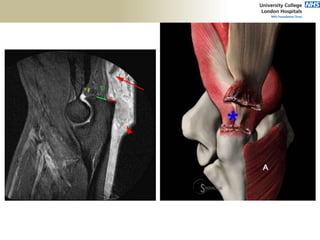

FABS MRI

Flexion/Extension

• Dominant=non-dominant

- Age, sex, muscularity

• Anterior offset of distal humerus

• Uniaxial hinge

• Carrying angle 11-14deg

• Axis: abducted by 50% of CA

Pronation/Supination

• 80deg pronation

• 90degree supination

• Axis: radial head to ulnar head

• RH: Proximal migration of radius

with pronation

• OA: grip & grind

• Missed Essex-Lopresti Injury